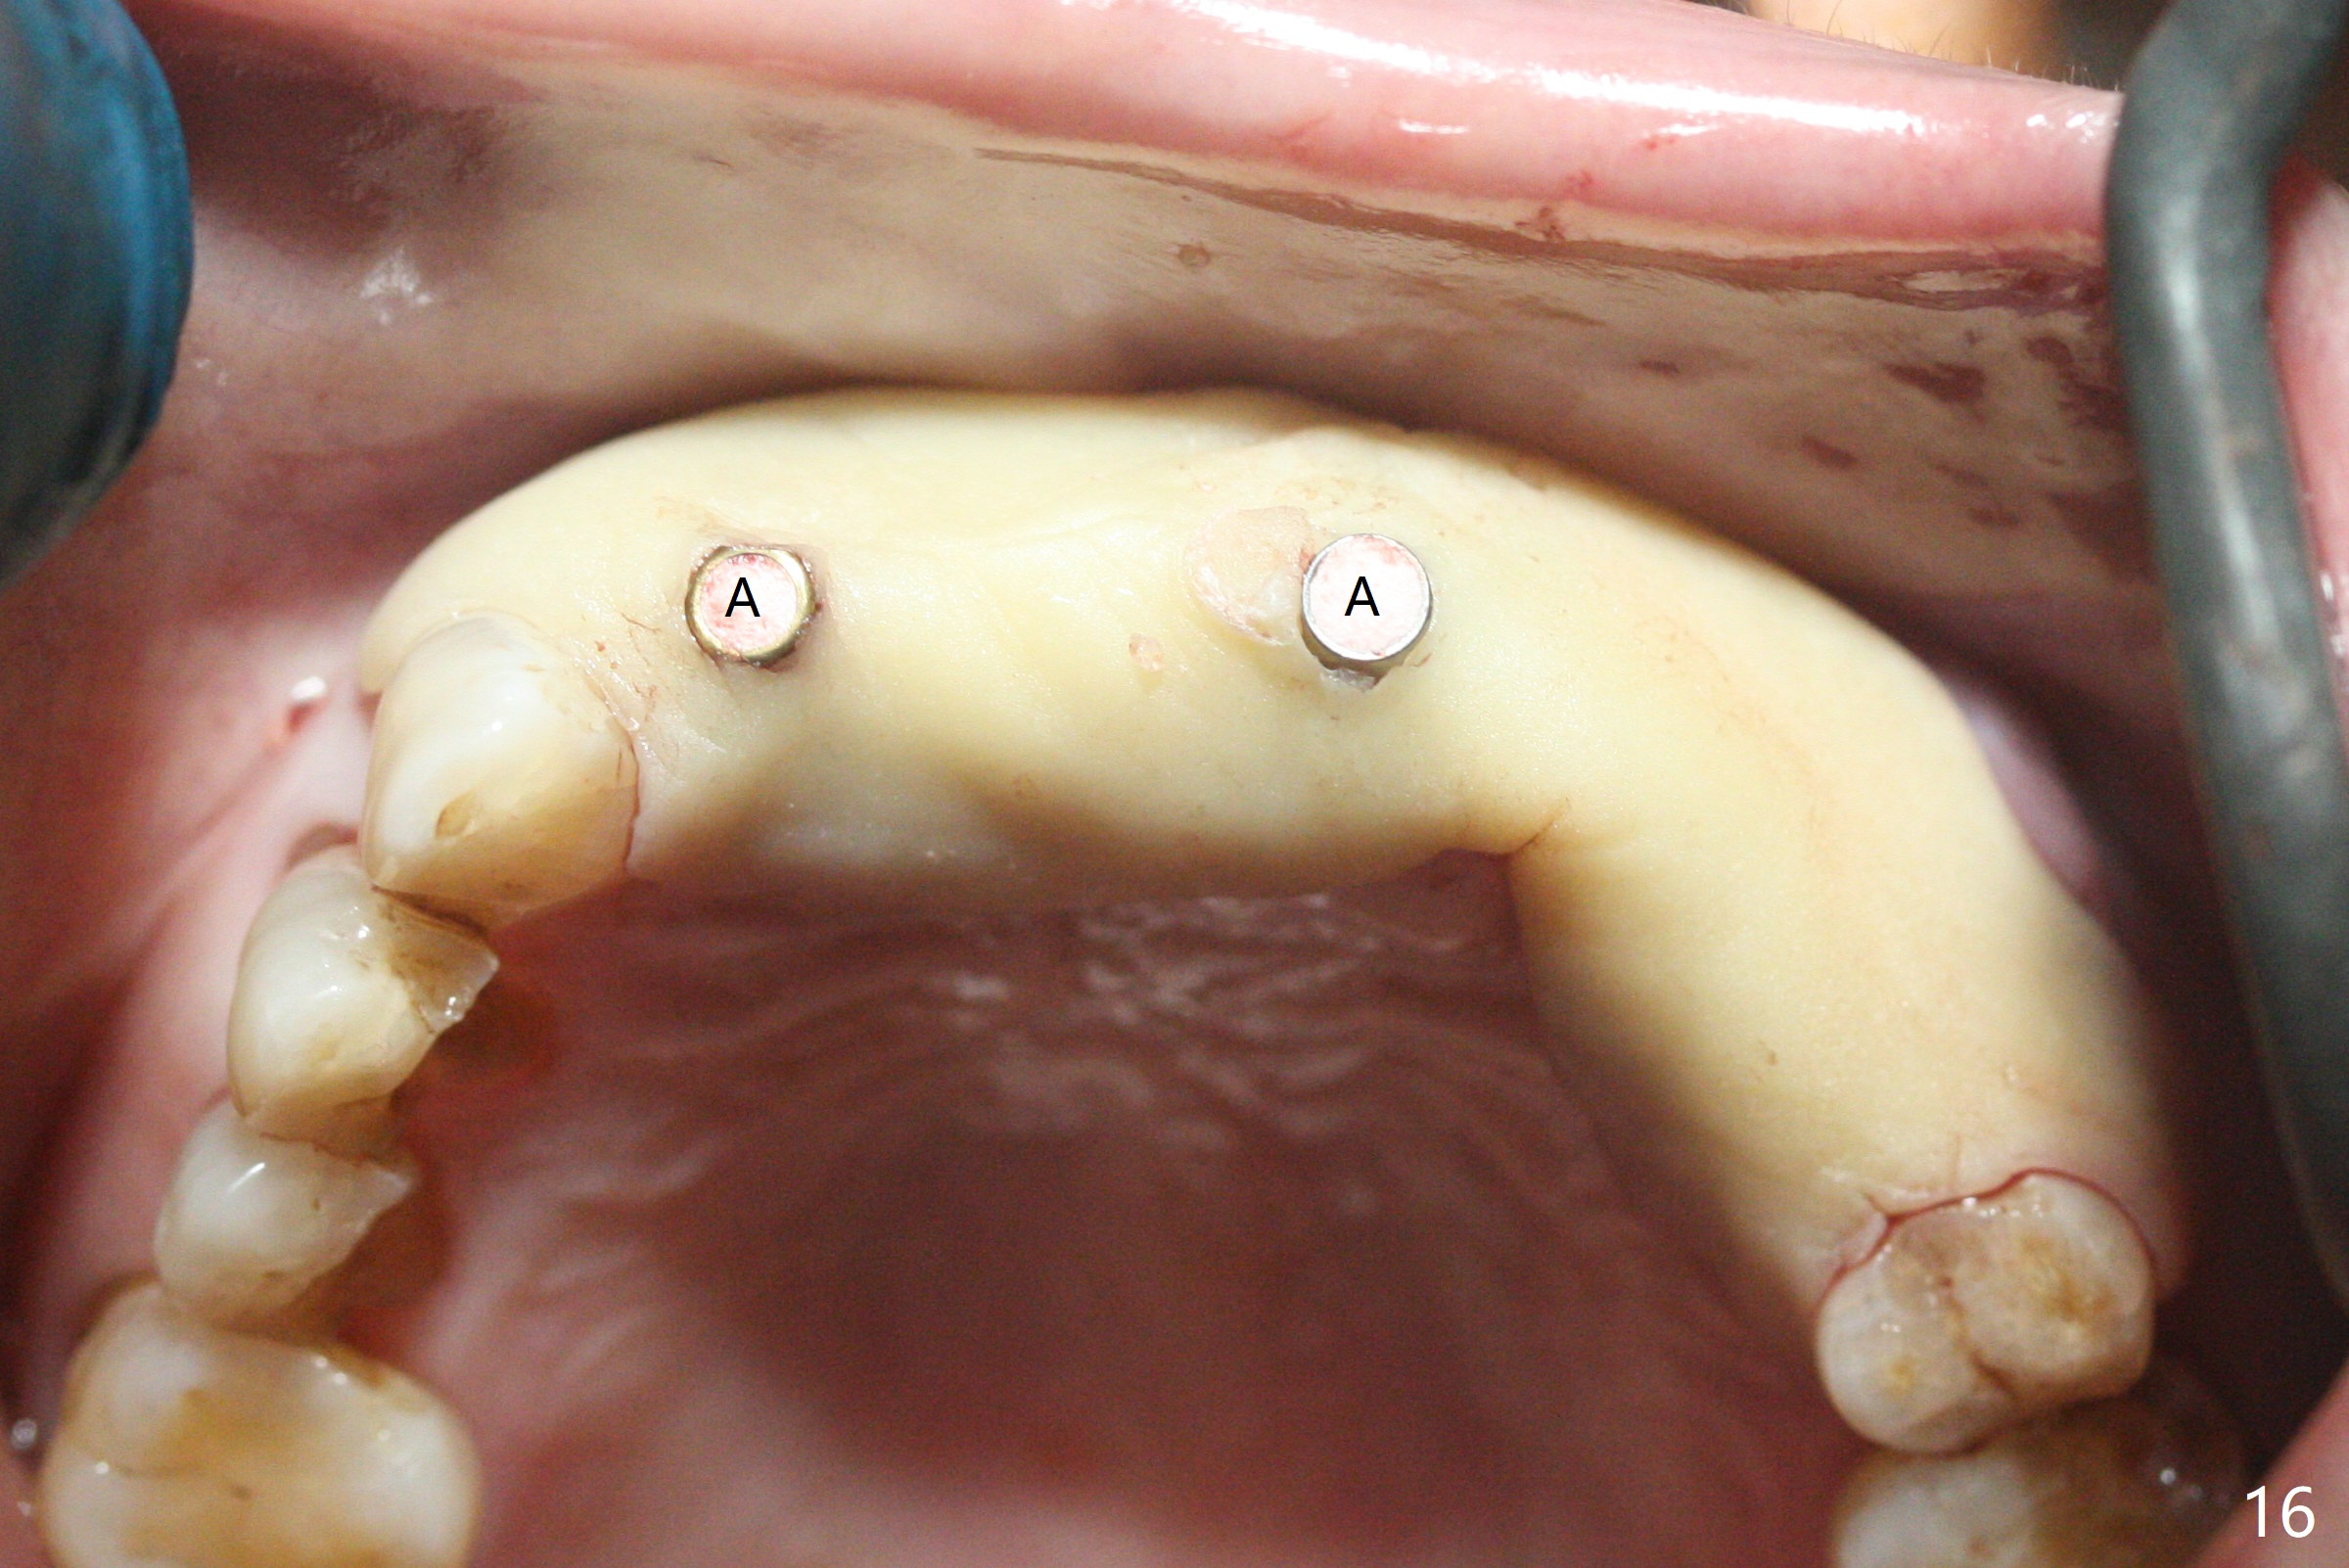

今天下午进入治疗室,粘性骨粉已制备:上清液来自红管(含促凝剂),离心3分钟(图一);再离心10分钟上清液就转变PRF,压制后,使用前剪成三块(图二:黑线),其中两块punch一个洞(图二:圆圈),插入7,9号牙基台固定;大块覆盖11/12号牙牙槽窝(图十四)。7,9,11,12号牙必须拔除(图三),然后在7,9,12种植。由于缺失左下磨牙,前牙垂直距离减少(图四)。完成9号牙位钻洞后,利用fixture mount(图五:M)植入植体,并留在原位固定导板(图六),然后7号牙种植,也留下fixture mount(图六:7,9),最后完成12号牙植入,但是后者扭力低,放置愈合螺帽(图九),而7,9号牙位放置修复基台(图七,八(使用5.5毫米profile drill后),好像基台没有完全就位。7号牙位更换基台似乎没帮助(图十),9号牙位再次放置同一个基台临床上仿佛有改变(比较图八与十二)。放置粘性骨粉后(图十一至十三),牙槽窝口覆盖PRF膜(图十四:P(A:基台)),最后使用树脂敷料固定骨粉和膜(图十五,六),基台帮助敷料固位,没有咬合干扰(图十七:*)。树脂敷料部分解决美观问题,一个月后撤除,如果植体仍有稳定性,可能制作7-10临时牙桥,可能部分维持或者恢复牙龈外形。术后一周病人主诉后面植牙和鼻底疼痛,11号牙根尖牙龈充血(图十八),轻度触痛,可能与术中尚未完全清创有关(图十九(术前CT 3D图像))。再服用Amoxicillin一周,症状好转,鼻底轻度触痛(图二十)。术后1.5月没有任何不适,撤除树脂敷料,7号牙基台(袖)显得太长,换一个短的(4.5x4(5)(图十,十一)->4x4(3)毫米)毫米),植骨好像愈合正常(图二十一:*)。7号牙换了短的基台,9号牙基台高度调整后,与对合牙有足够空间做临时牙桥,最好8,10号牙位牙龈应该凹陷(图二十二:*),有pontic外形。另外9号牙基台颊侧牙龈边缘有所修整,临时牙桥准备。先做7-10临时牙桥,理想临时牙桥pontic处树脂应该多些(图二十三:白线)压迫牙龈形成凹陷。11,12号牙牙槽窝在树脂(Bosworth)敷料下也正常愈合(图二十四)。